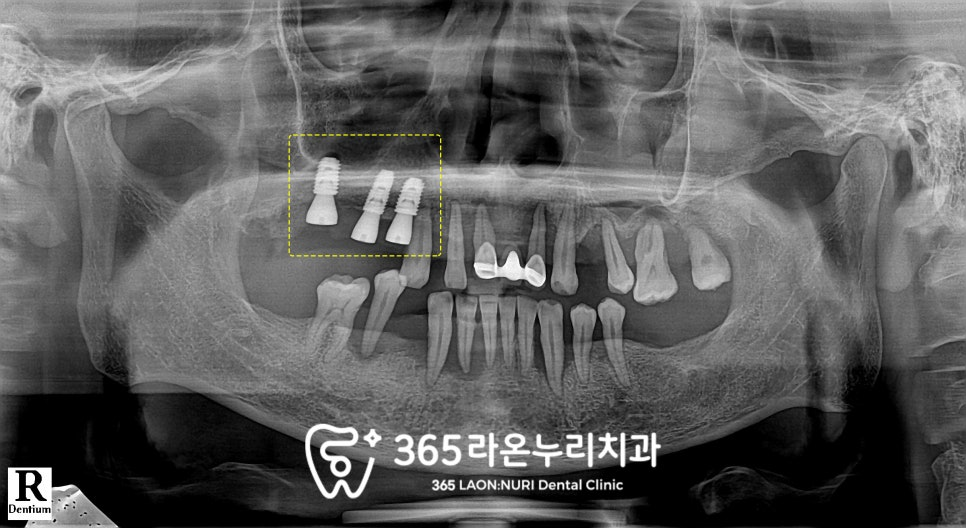

파노라마를 찍게 되는데

이 과정에서 치조골의 높이와

치아 뿌리 끝 염증까지 확인할 수 있습니다.

엑스레이를 통해 살펴보니

치조골의 높이가 상당히 낮아져있으며

위아래가 제대로 물리는 곳이 없을 만큼

교합도 불안정합니다.

파노라마는 구강 전체가 나오는 사진이라

치근단 사진을 찍어 한 번 더 살펴보았습니다.